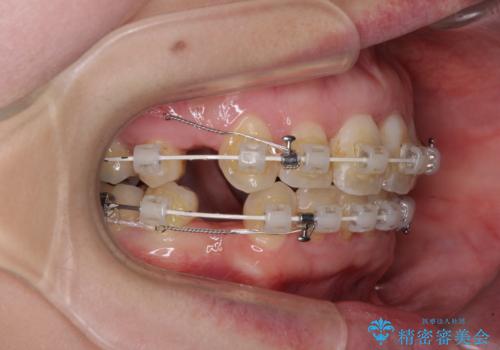

- 出っ歯と口の閉じにくさ、デコボコを気にして来院された患者様です。

口元の突出感を改善するため、上下左右第一小臼歯4本の抜歯を行い、ワイヤー装置による矯正治療を行うこととしました。

上下前歯の距離が大きかったため、上下の歯が接触するまでに時間がかかりました。

それでも目安である2年半で終えることができ、患者様には大変満足していただけました。